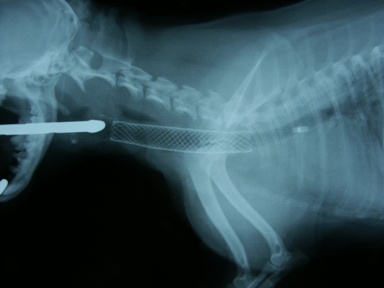

図2 気道ステント留置例。写真は気管虚脱GradeIVを示すヨーキーの症例の初診時X線写真。胸郭前口部の気管が完全に扁平化している。

図4 同症例のステント展開直後のX線写真。気管が十分開存された。